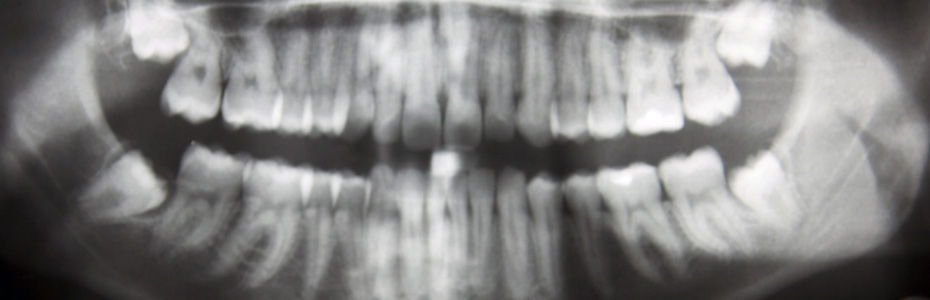

Oral Surgery

Oral surgery treats the complex structures of the jaw and teeth.